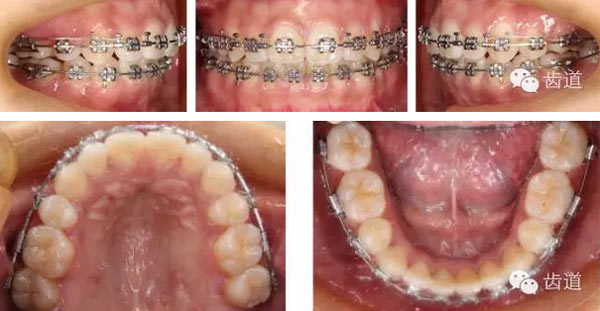

矯治結(jié)束后口內(nèi)像

拔牙模式:患者25腭側(cè)完全錯(cuò)位后左上磨牙前移,使左側(cè)磨牙關(guān)系接近完全遠(yuǎn)中,而28牙冠較小,故正畸矯治拔除了14,18,25,28,35,45,于上頜第一與第二磨牙間頰腭側(cè)各植入微種植體支抗,運(yùn)用微種植體支抗壓低上磨牙,內(nèi)收前牙并糾正中線,適當(dāng)遠(yuǎn)中移動(dòng)左上牙列。下頜第三磨牙矯治前并未拔除是因?yàn)槠渖L(zhǎng)對(duì)矯治有利,建議其矯治后拔除。

橫向不調(diào):牙弓寬度輕度不調(diào)的解決在于上頜適當(dāng)?shù)臄U(kuò)弓與后退左上牙列,以及下頜適當(dāng)?shù)目s弓與下磨牙前移,矯治后上頜磨牙寬度由41.8mm變?yōu)?3.1mm,下頜磨牙寬度由39.6mm變?yōu)?7.8mm。

矢狀向、垂直向及開(kāi)合:上頜磨牙壓低及下頜磨牙前移產(chǎn)生的楔形效應(yīng),上前牙適量?jī)?nèi)收產(chǎn)生的鐘擺效應(yīng),以及肌功能訓(xùn)練的綜合作用解除了患者的開(kāi)合,并使下頜逆時(shí)針旋轉(zhuǎn),矯治后患者的側(cè)貌得到極大改善,達(dá)到了近乎“頦成形”的效果。